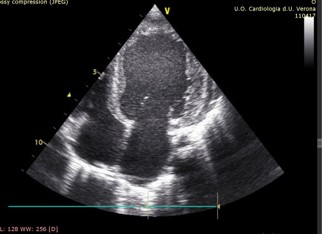

At 2 years of age, a gallop rhythm was detected on cardiac auscultation, raising concerns about underlying cardiomyopathy (CM). Echocardiography revealed hypertrophic cardiomyopathy (HCM) with diastolic dysfunction and mitral valve regurgitation (E/E’ 12.5, LVEDD 32 mm, z-score +1,24; LVESD 15 mm, z-score 1,20, IVS 6 mm, z-score +1,30, LVPW 6 mm, z-score +2,26, LVFS 53%, LVEDV 56 ml/m2, LVESV 26 ml/m2, LVEF 54%) (Figures 1a & 1b).

Figure 1b: Concentric hypertrophic left ventricle.